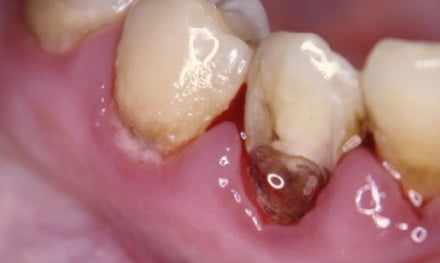

Пришеечный кариес: фото до и после

Как выглядит данный тип кариеса, предлагаем к просмотру подробные фото зуба.